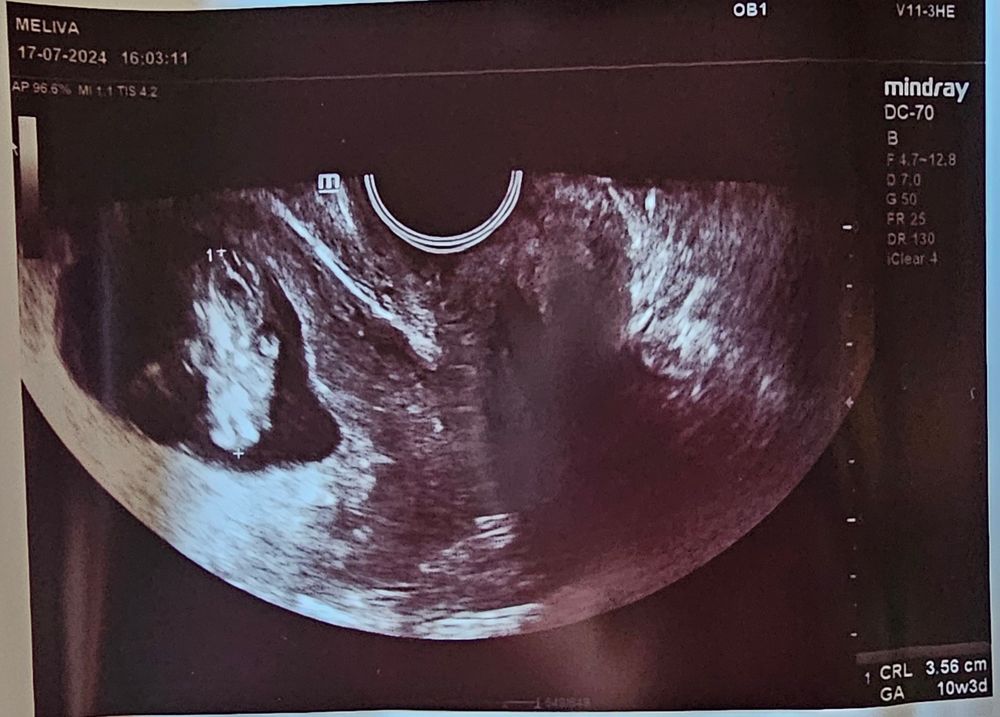

10+3 УЗИ 🥹💕🌸

Вчера была на УЗИ, поставили на учет, заказали анализы, поставили время первого скрининга (29.07).. второй раз увидела эту крошку 🥹

Поплавала, пошевелилась, помахала ручками🥹 После 2 замерших на раннем сроке, видеть, как этот маленький человечек плавает, шевелет ручками и ножками.. очень необычное и трогательное чувство. Внутри сразу трепет какой-то появился и, конечно, немного страха, что внутри меня такая малюточка. 💕💞 В каком-то смысле даже не верится, как сон какой-то.. очень люблю эту кроху и жду нашей встречи🌸💕